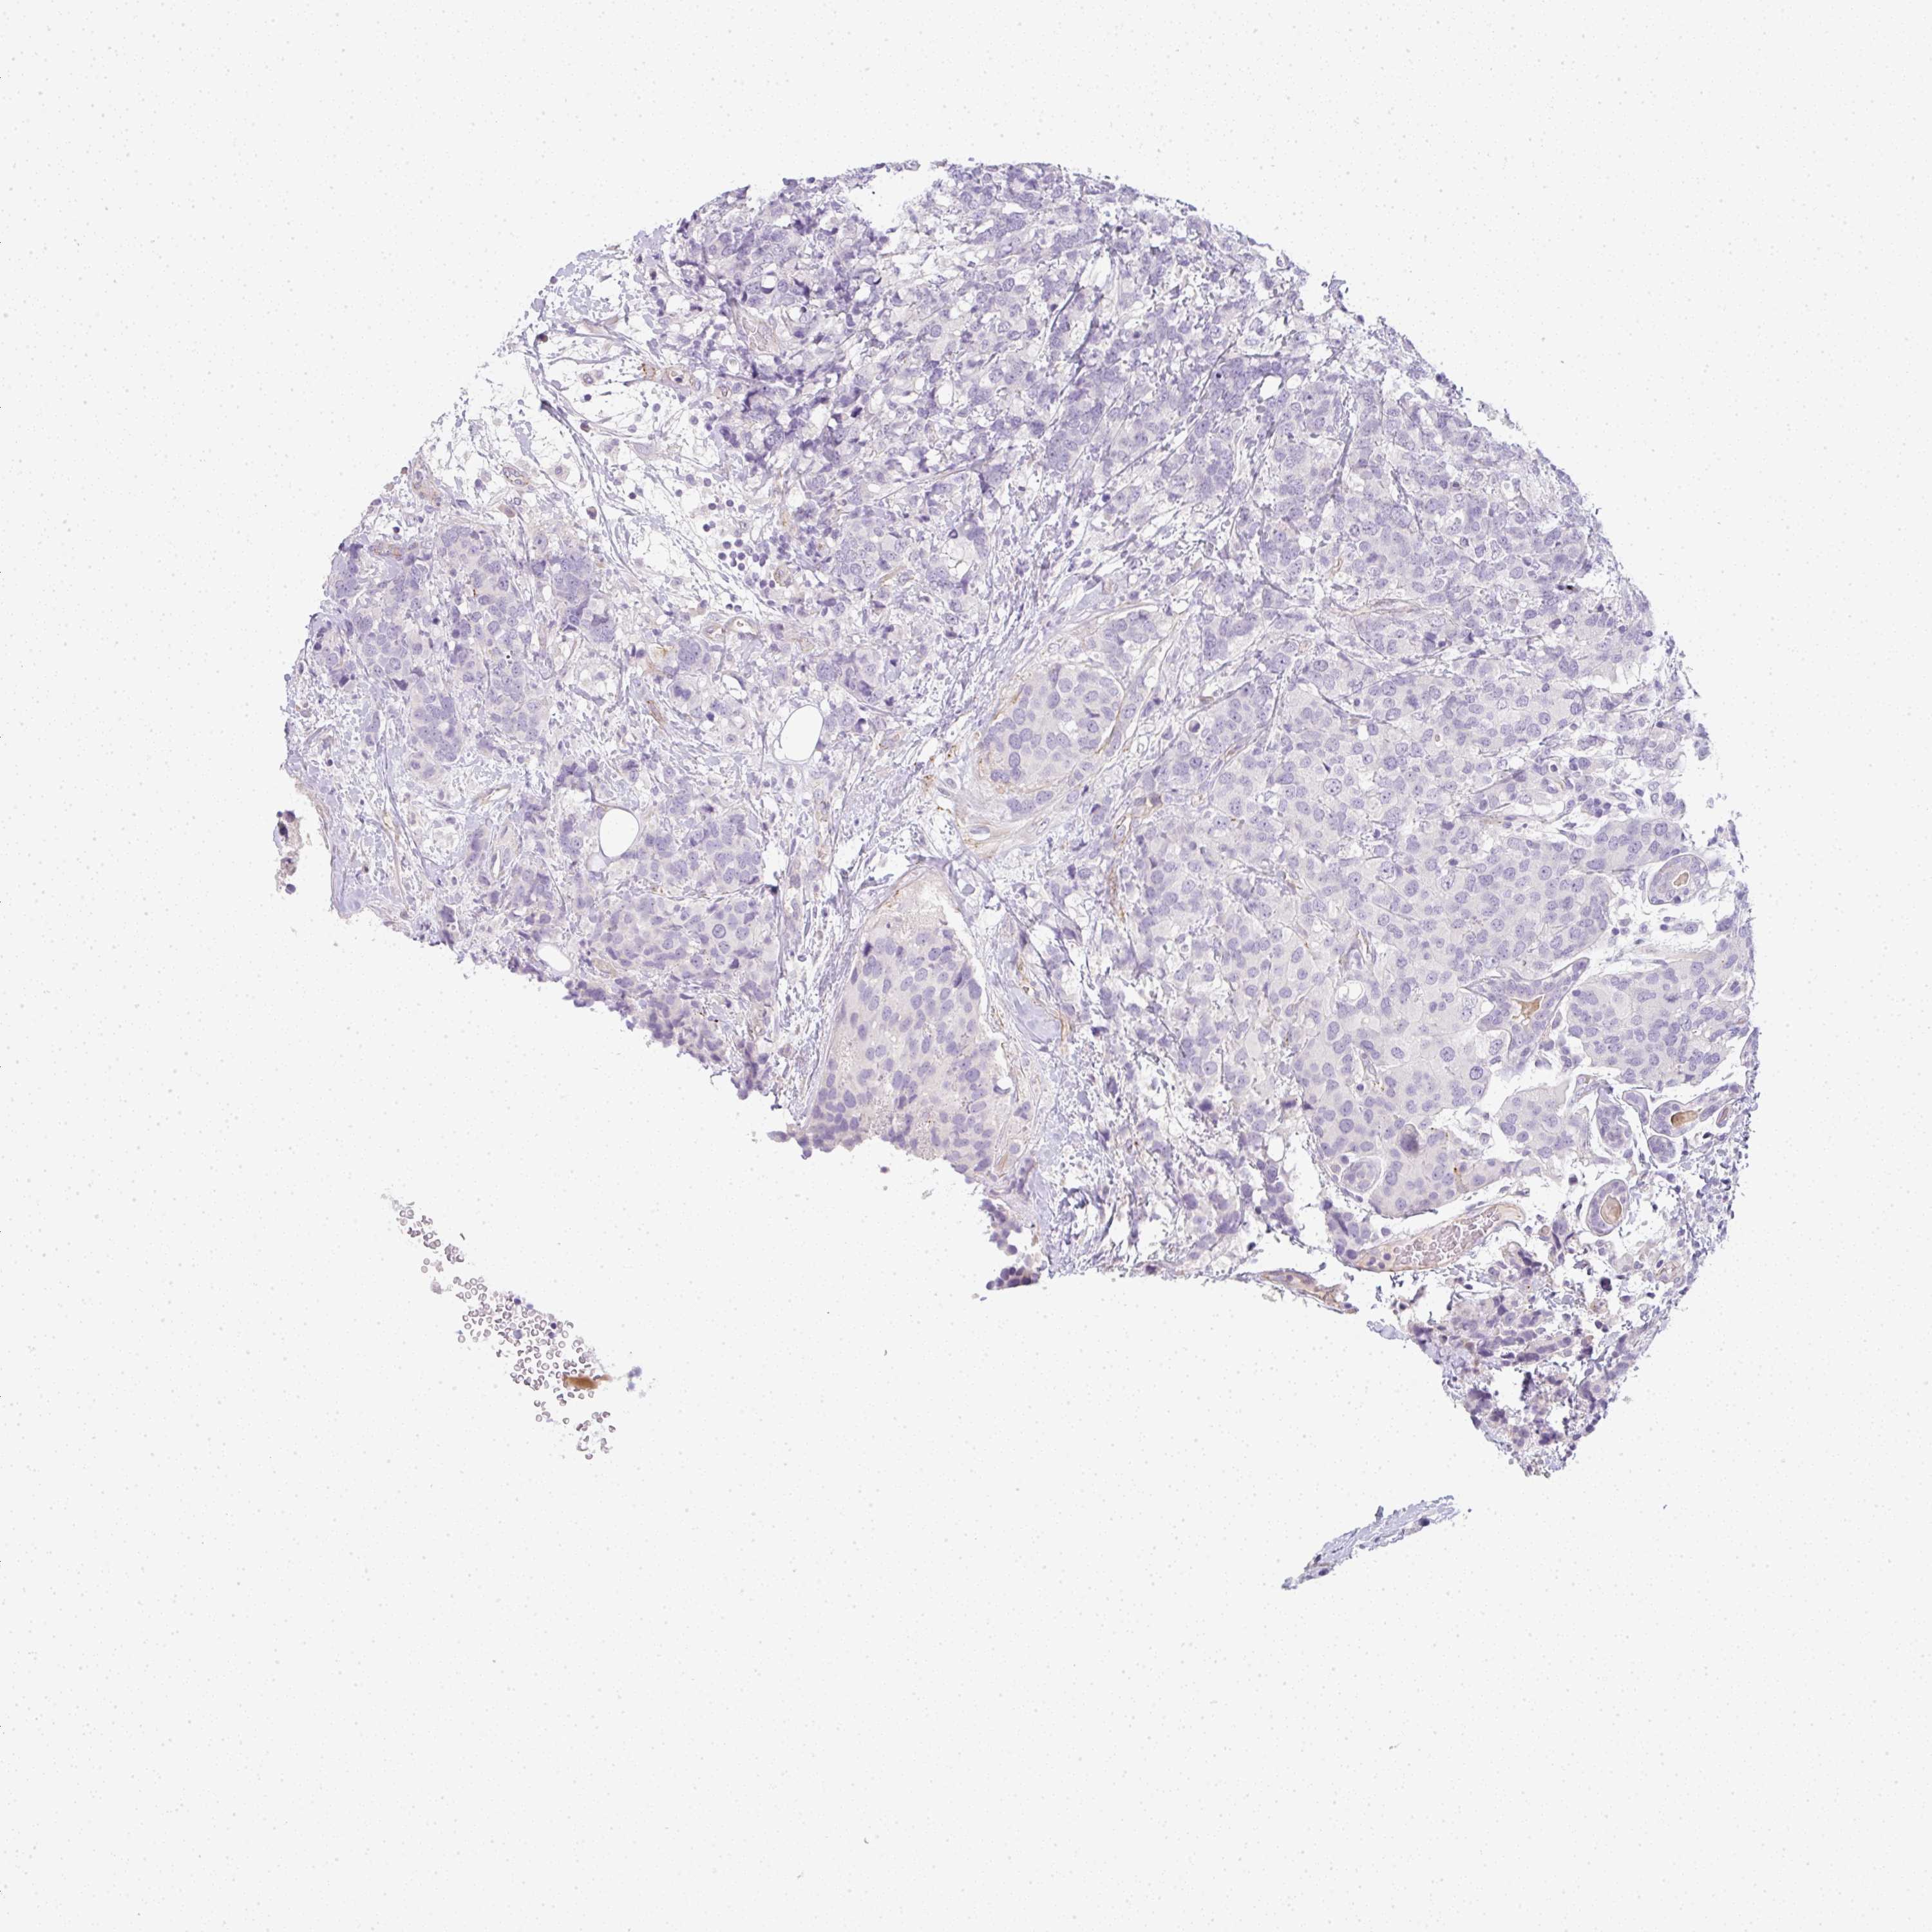

BRCA TCGA BRCA VALIDATION PROTEIN EXPRESSION

ANTIBODIES

AND

VALIDATION